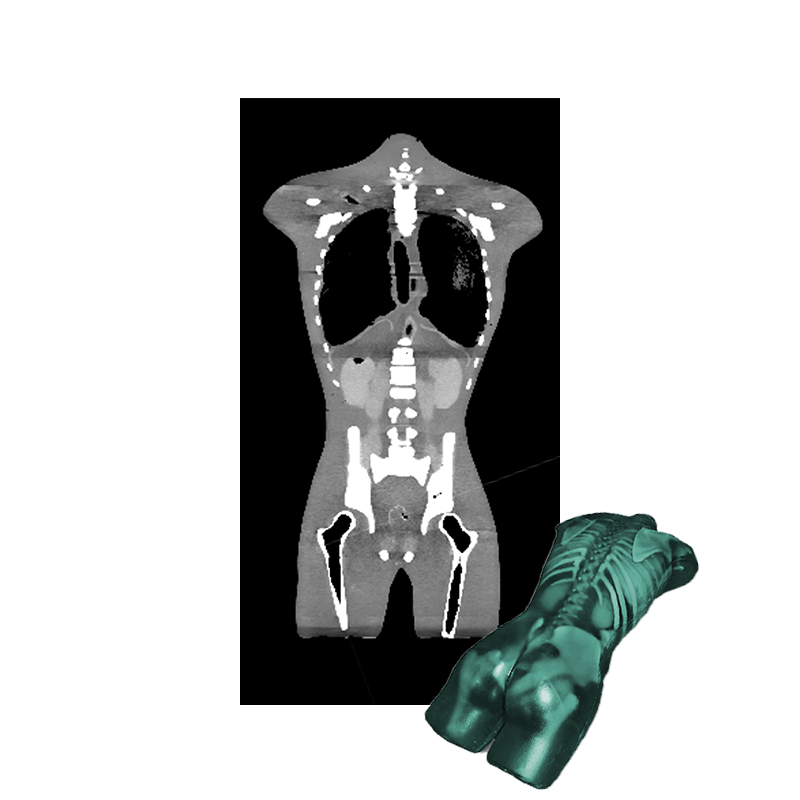

Anatomy:

- Complete Spine

- Complete Ribcage

- Shoulders & Clavicles

- Pelvis

- Partial Femur Bones

- Trachea

- Heart

- Lungs

- Diaphragm

- Liver

- Gallbladder

- Stomach

- Kidneys

- Spleen

- Pancreas

- Large and Small Intestines

- Bladder

- Prostate

Adult Torso for X-Ray CT, Ultrasound is designed based on an average anatomy of an adult healthy human male. It is compatible with X-Ray/CT and Ultrasound. The skeleton is made from individually cast bones from a realistic patented epoxy-based composite material with vertebrae that have a realistic three-layered structure with inner porosity. An ideal phantom for training ultrasound technicians and other medical students.